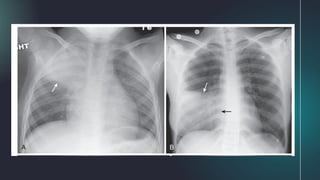

2. Compressive Atelectasis (Passive)

● due to passive compression of the lung can

be caused by:

○ poor inspiratory effort in which there is

passive atelectasis of the lung at the

bases (Fig. A)

○ large pleural effusion, large

pneumothorax, or a space-occupying

lesion (such as a large mass in the

lung) (Fig. B)

● when caused by a large effusion or

pneumothorax, the loss of volume associated

with compressive atelectasis may balance the

increased volume produced by either fluid (as in

pleural effusion) or air (as in pneumothorax)

● in an adult patient with an opacified hemithorax,

no air bronchograms, and little or no shift of the

mobile thoracic structures, it is important to

suspect an obstructing bronchogenic

carcinoma, perhaps with metastases to the

pleura